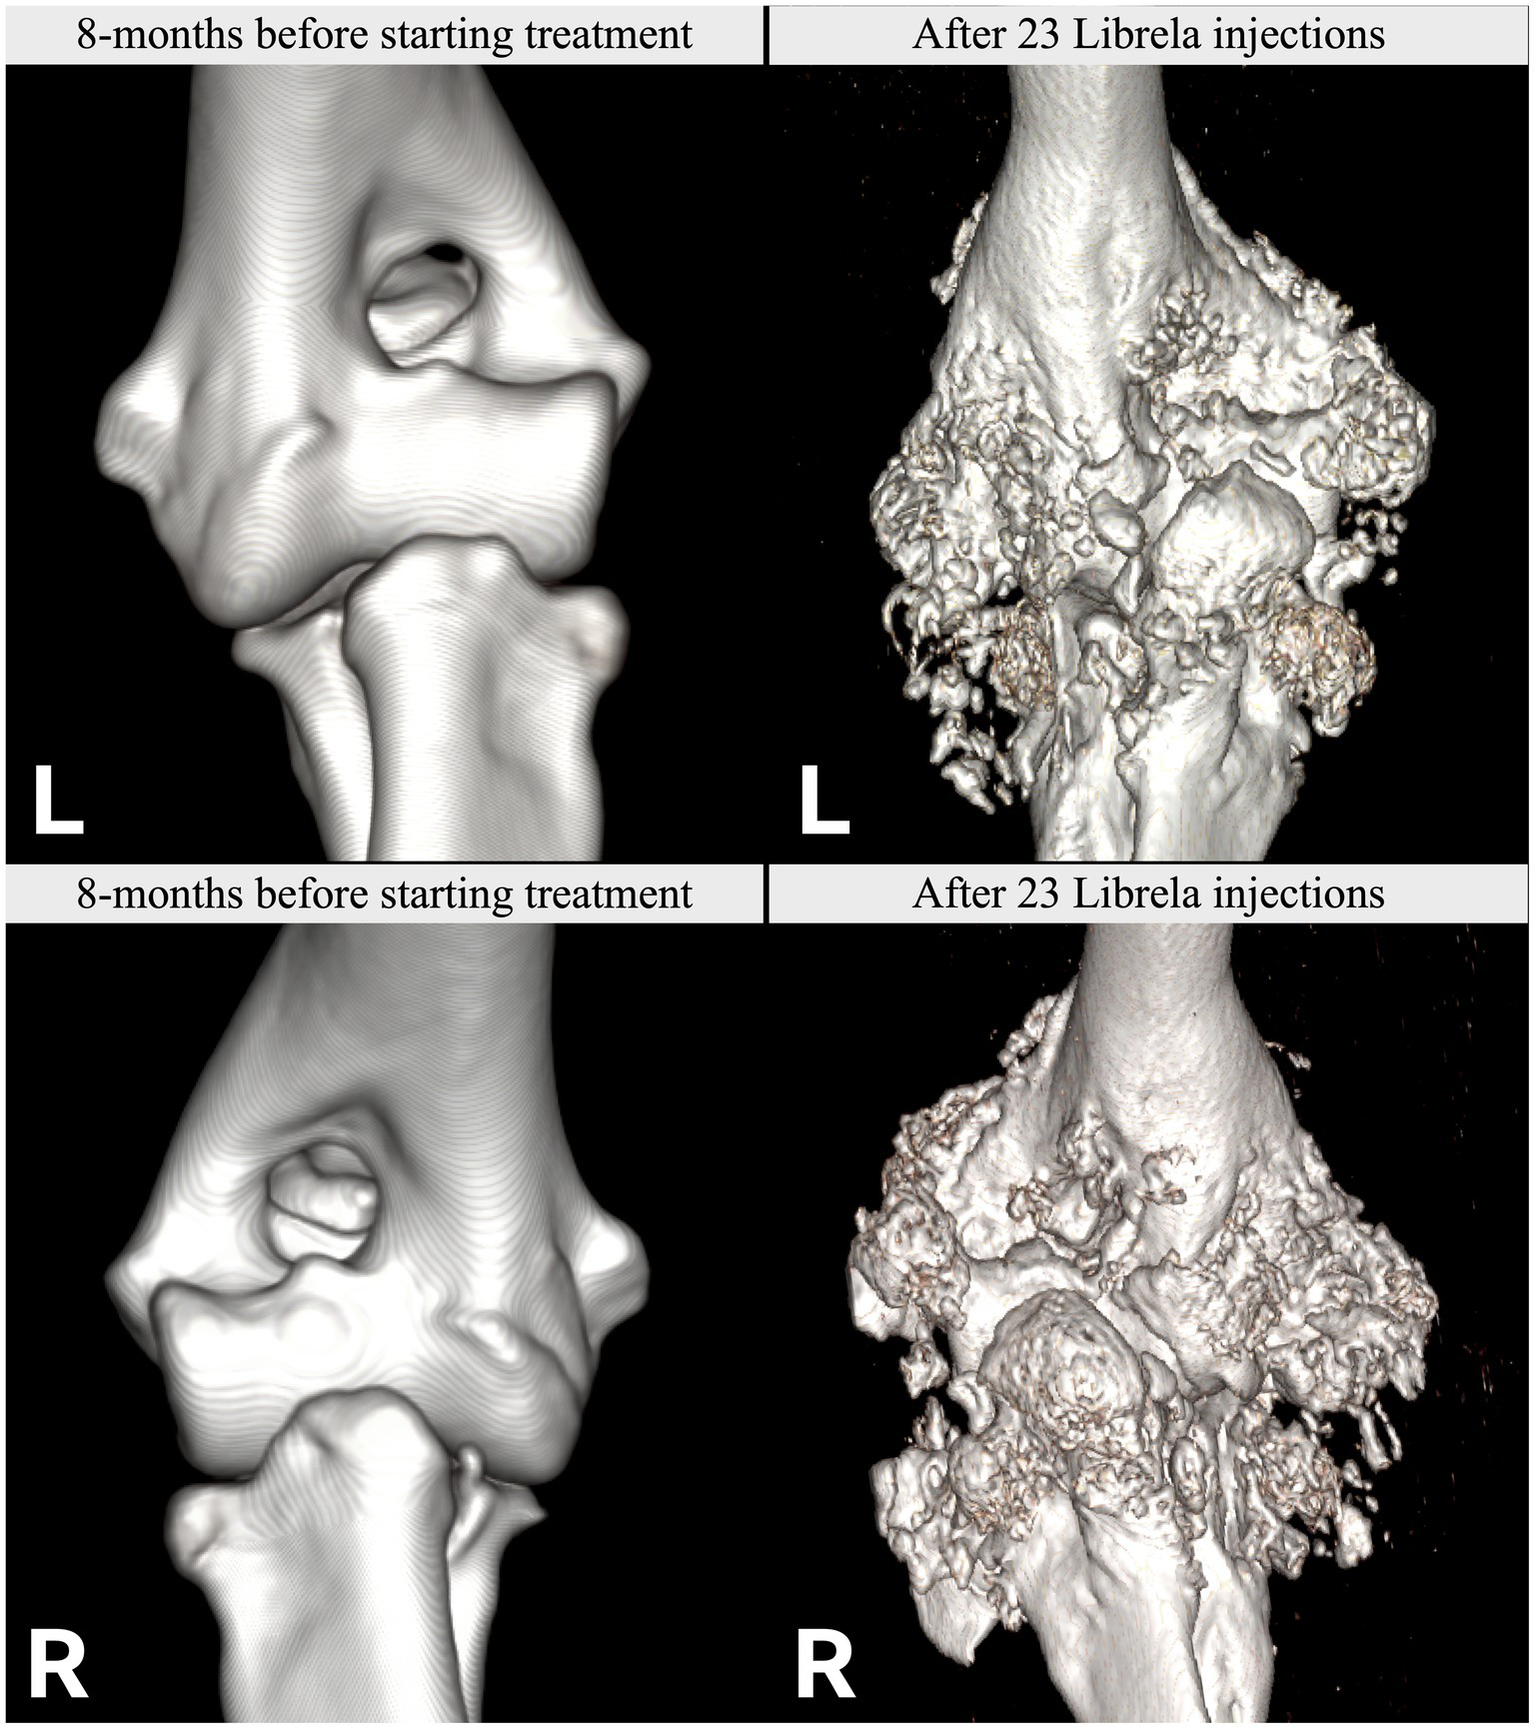

Figure 7

Left (L): Normal pre-treatment CT scans from Case 11, a 7.5-year-old Labrador Retriever. Post-Librela CT scans revealing fulminant periarticular osteophytosis. Right (R): Post-Librela CT scans revealing fulminant periarticular osteophytosis. AER: The attending specialist filed an AER to the VMD specifying their suspicion of RPOA. This report was shared with the MAH, who filed an AER for non-serious arthritis, with an outcome of recovered/resolving (Supplementary Figure S5).

Figure 8

Case 13 is a Staffordshire Bull Terrier with no history of trauma. (A–D) Pre-treatment CT scans showed mild elbow arthrosis and excluded HIF. (E–H) Post-Librela radiographs demonstrated severe left elbow arthrosis and a right lateral HCF with an atypical medial epicondylar periosteal reaction. AER: Given the patient’s age and breed, which is not predisposed to HCF, the attending specialist submitted a report to the MAH specifying a suspicion of RPOA. The MAH filed a report with an incorrect diagnosis of “osteosarcoma” (Supplementary Figure S7).